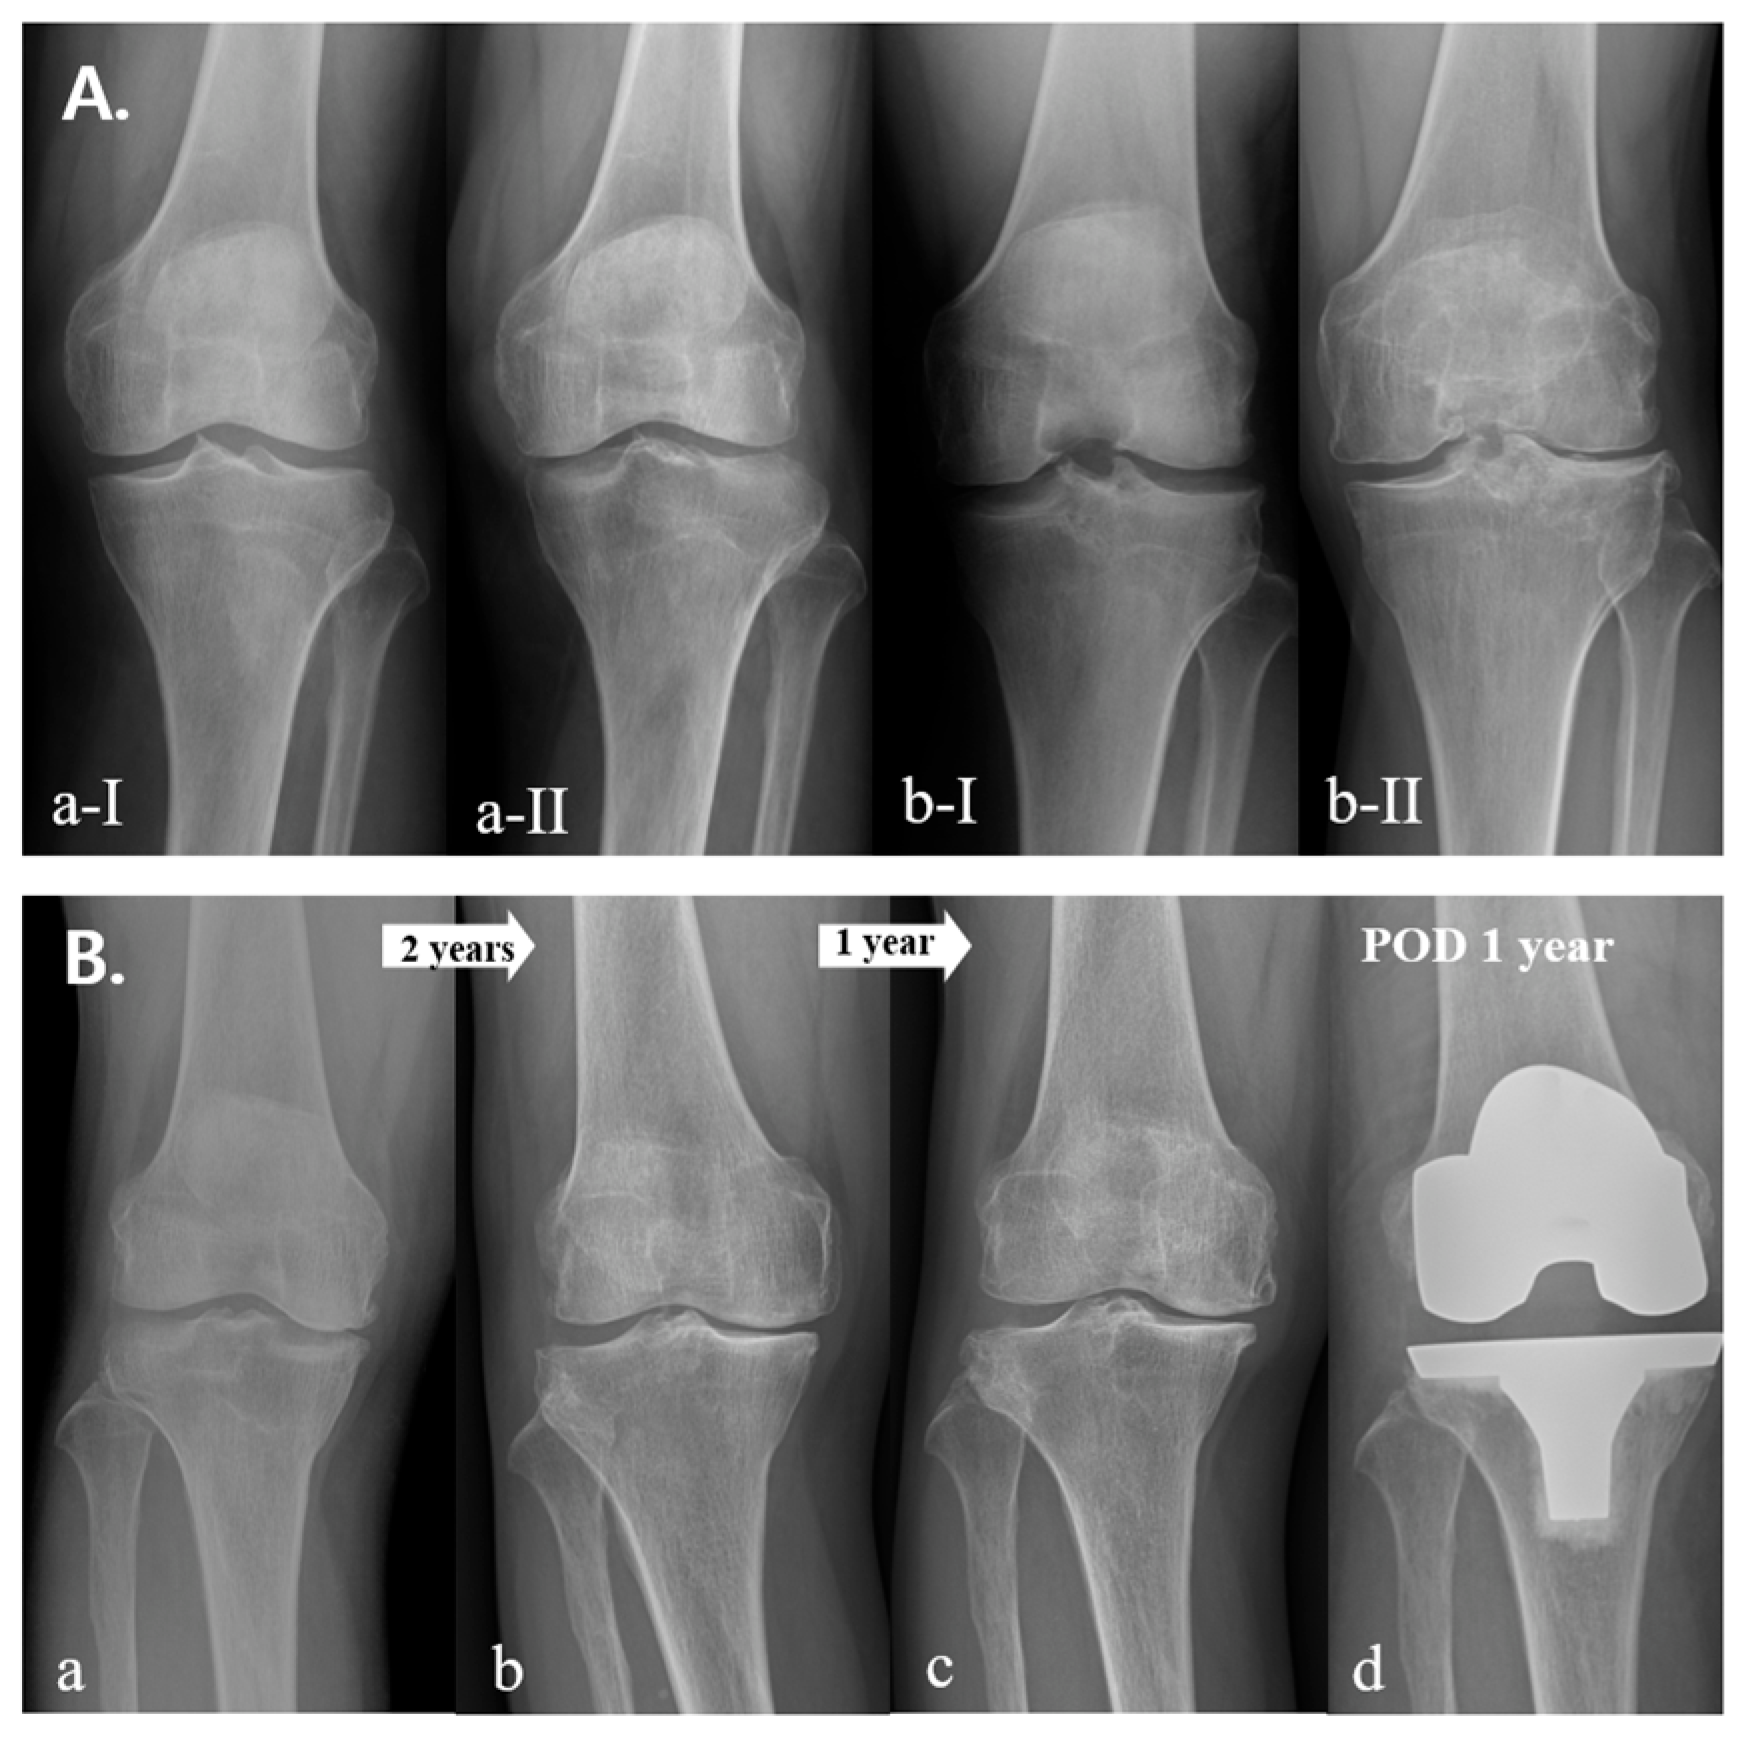

3. Results